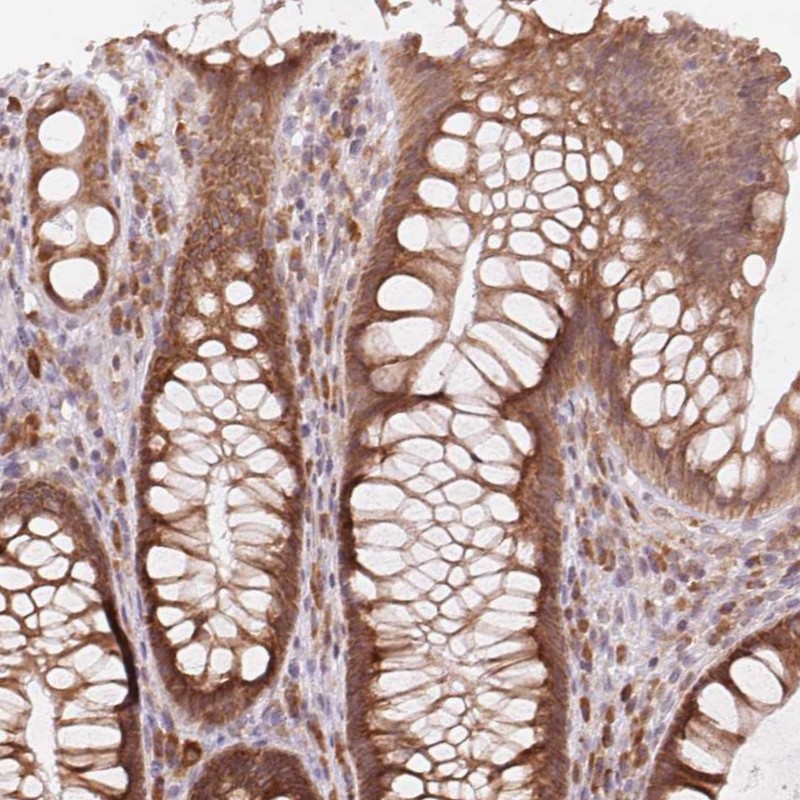

Immunohistochemical staining of human rectum shows moderate cytoplasmic positivity in glandular cells.